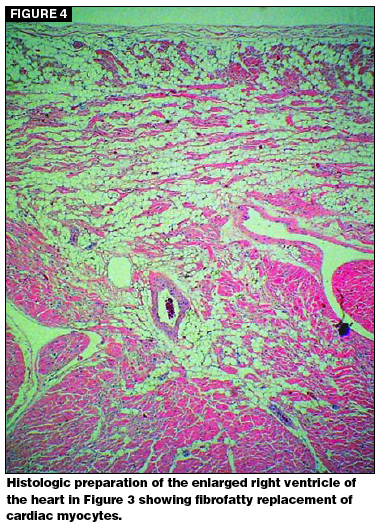

Arrhythmogenic right ventricular cardiomyopathy is also called ARVC for short or boxer cardiomyopathy because it occurs predominantly in boxer dogs. Arrhythmogenic right ventricular cardiomyopathy ARVC runs in families of boxers and has been reported in humans and cats as well. Life expectancies are extremely variable but with.